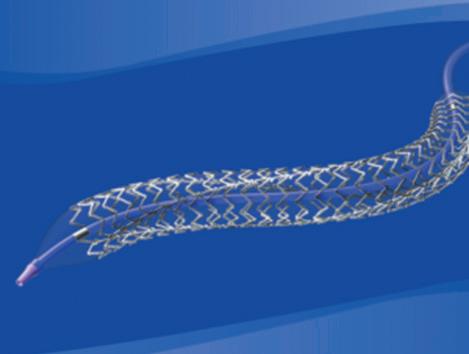

First, Boyle referenced data from the landmark EVAR-1 trial, noting that patients who were randomised to endovascular aneurysm repair (EVAR) “had far greater numbers of interventions out to 14 years” than the patients who received open repair.

Acknowledging the age of the EVAR-1 data as a weakness of his argument, Boyle subsequently moved on to newer EVAR evidence. Specifically, the presenter spoke on results from the VQI VISION study regarding the AFX graft (Endologix). The 2022 data, which illuminate reintervention and rupture rates with an early iteration of the device in the USA, were published by Goodney et al in the British Medical Journal

“When we fix an aneurysm, we’re trying to do it to prevent rupture, but the early AFX graft had a near 40% reintervention rate at eight years and a 10% rupture rate at 10 years,” Boyle informed the ESVS audience, summarising the VQI VISION data. “So, 10% of the patients treated with this device ended up rupturing their aneurysm.”

In light of these data, Boyle remarked: “We’re fixing aneurysms, but we’re not really fixing them.”

Towards the close of his presentation, Boyle went back to Endologix, this time focusing on Nellix. “We got our fingers burnt with this device,” the presenter acknowledged. He recalled a sense of optimism in the early stages of using this device. “We all felt at the start this was a device that may change practice,” Boyle remembered. In the end, however, the presenter stressed that “a lot of patients came to harm as a result of being treated with this device”.

Sharing some data on the device from his centre in Cambridge—specifically from a 2021 EJVES paper by Singh et al—the presenter noted that, at six-year follow-up, only 32% of patients still had freedom from device failure and there were “quite a few ruptured aneurysms”.